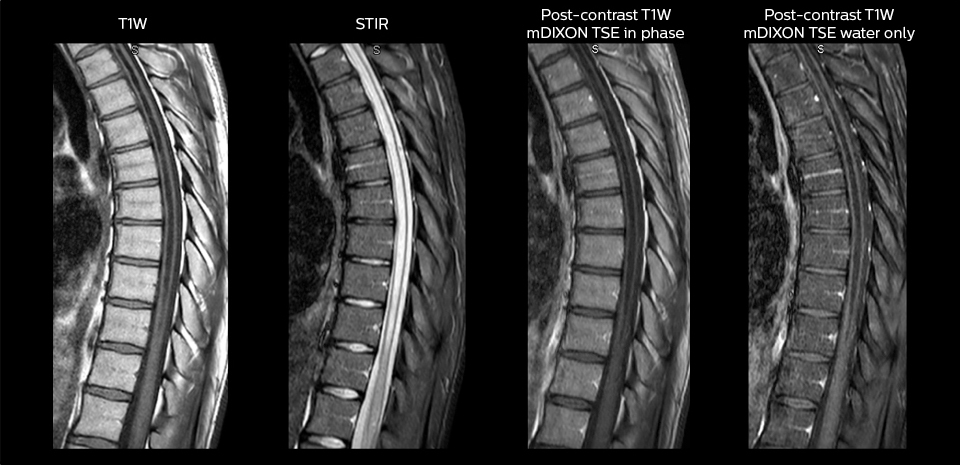

Including mDIXON TSE for robust fat suppression

“We use mDIXON TSE extensively in our spine imaging in the emergency room,” says Dr. Karis. “It’s particularly nice in that it is very robust with regard to susceptibility type of problems that would come up with traditional spectral fat-saturated images; these problems are essentially eliminated with the mDIXON technique. In our ED environment it’s really nice to have the fat-free imaging that goes along with the mDIXON technique.

“For the thoracic and cervical spine routine non-contrast exam, for example, we perform one mDIXON T2 TSE sequence, which provides us with two outputs: the fat-and-water-together T2-weighted images, as well as the water-only sagittal T2-weighted images. And then we also perform an axial gradient echo exam.”